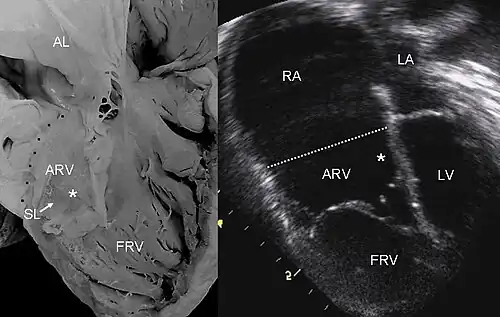

| Pathological specimen and ultrasound image of a heart with Ebstein's anomaly: Abbreviations: RA: right atrium; ARV: atrialized right ventricle; FRV: functional right ventricle; AL: anterior leaflet; SL: septal leaflet; LA: left atrium; LV: left ventricle; asterisk: grade II tethering of the tricuspid septal leaflet | |

The annulus of the valve is still in the normal position. The valve leaflets, however, are to a varying degree, attached to the walls and septum of the right ventricle. A subsequent "atrialization" of a portion of the morphologic right ventricle (which is then contiguous with the right atrium) is seen. This causes the right atrium to be large and the anatomic right ventricle to be small in size.